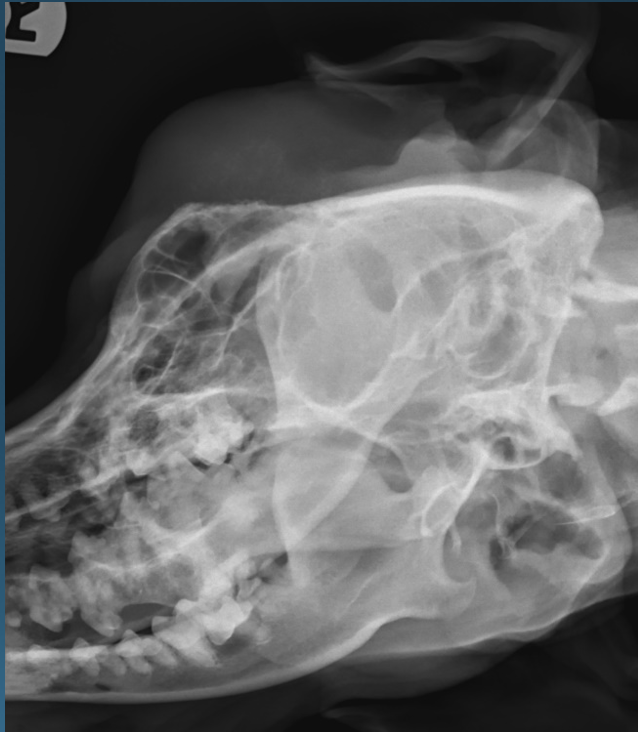

What is shown in this image?

craniomandibular osteopathy

What is shown in these images?

craniomandibular osteopathy -bone proliferation caudal and lateral to TMJs, but not ON the TMJ joints themselves